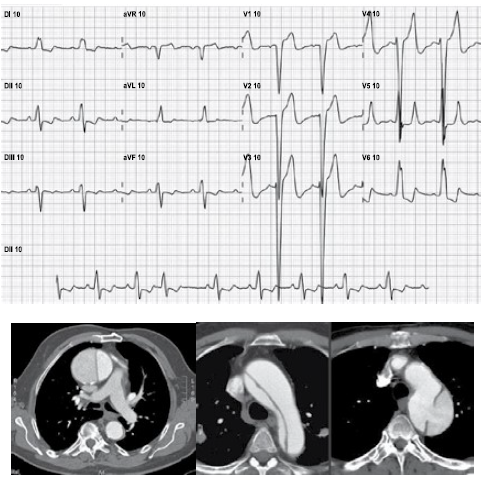

Homem, 65 anos, com histórico de hipertensão arterial, refere dor torácica retroesternal de forte intensidade e contínua, há cerca de 1 hora, acompanhada de sudorese e mal estar. Exame clínico: ausculta pulmonar e cardíaca estão normais; PA = 160 x 95 mmHg; FR = 20 ipm; temperatura axilar = 36,7 ºC; SpO2 = 98%. Foram realizados eletrocardiograma e angiotomografia de tórax, que encontram-se ilustrados a seguir.

enunciado 451166-1

A conduta mais apropriada neste momento, deve ser: